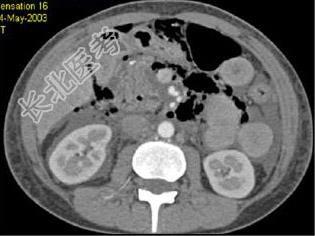

- 单项选择题根据所提供的图像,最可能的诊断是 ( )

A、穿孔后气腹

B、正常结构

C、肝炎

D、胰腺炎

E、以上都不是